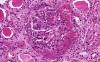

Kidney- Area 1: Concentric intimal thickening is well demonstrated in this image.

·         Concentric intimal thickening of blood vessels (hyperplastic arteriolitis): There is extensive intimal thickening due to a proliferation of elongated, concentrically arranged smooth muscle cells and layers of concentric collagen. Pale staining substance probably proteoglycans and plasma proteins are also present in these concentric thickenings. Histologically, these vessels resemble the cross section of an onion (onin-skinning of vessels). (Kidney- Area 1 and 2)